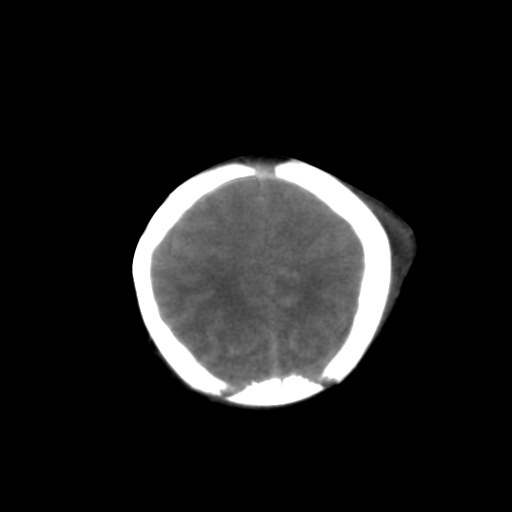

男,3天,患儿为剖腹产,生后嗜睡、拒乳。

1)考虑hie。2)sah?。3)右侧颞顶枕部及左侧颞顶部头皮血肿。

1、右侧颞顶枕部及左侧颞顶部头皮血肿。2、第五第六脑室。3、新生儿,脑白质密度还算可以,也无蛛血,不考虑hie。

脑室系统及脑沟裂闭塞,弥漫性脑密度减低,支持考虑hie,建议复查。右侧颞顶枕部及左侧颞顶部头皮血肿,另不除外胼胝体发育不良,复查